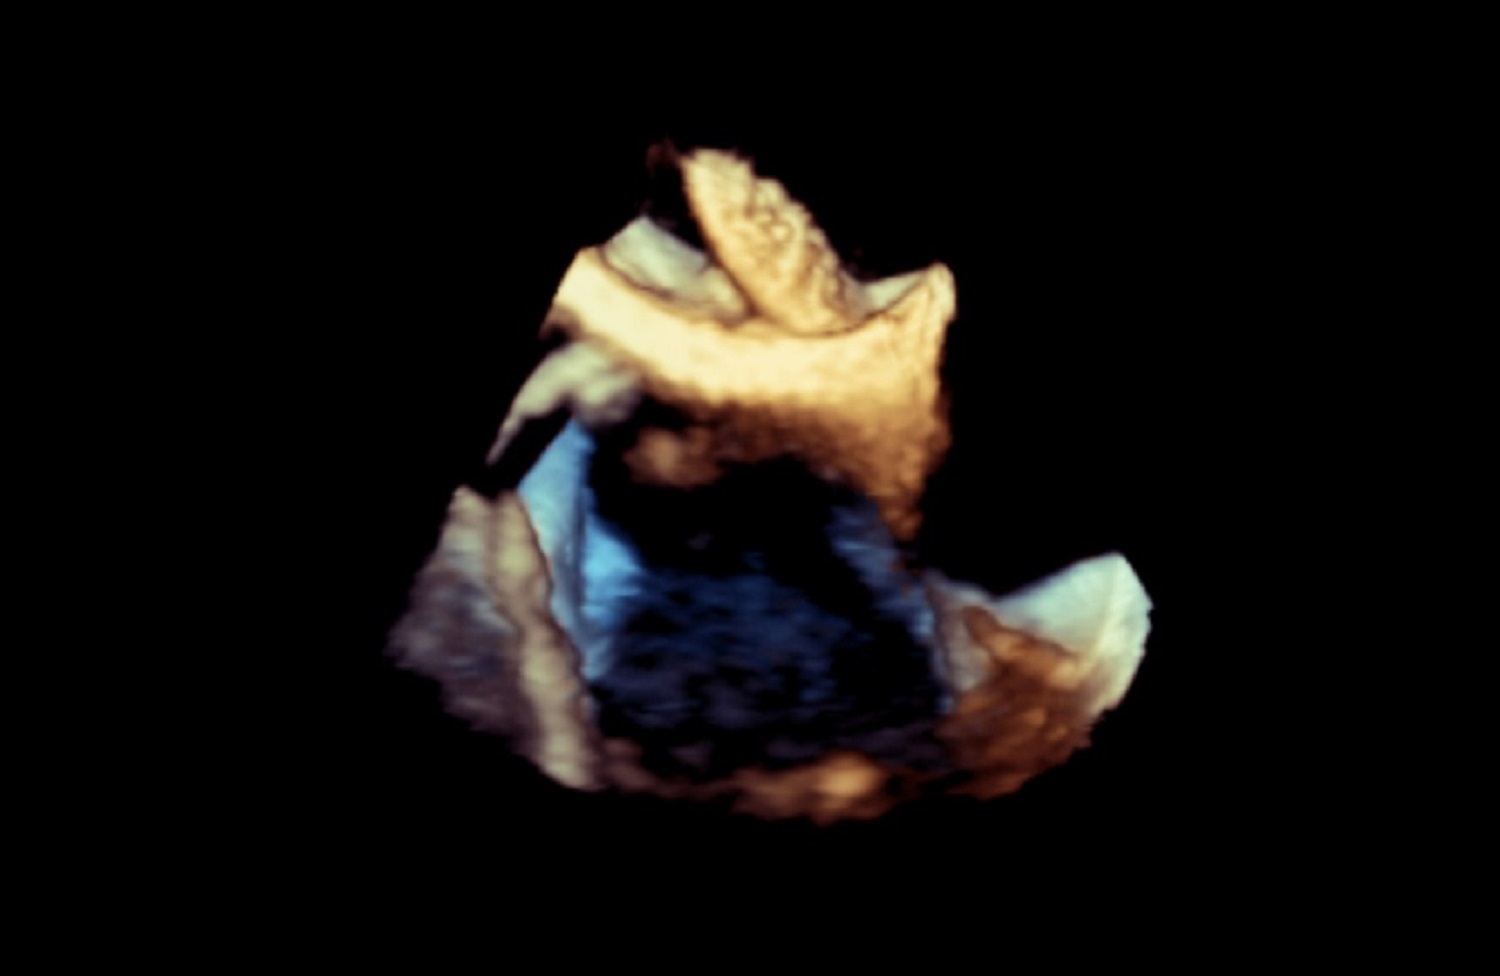

Dzięki wykwalifikowanemu personelowi i nowoczesnemu sprzętowi w Klinice wykonywane są również przezskórne zabiegi zamknięcia ubytków przegrody międzyprzedsionkowej typu II oraz drożnego otworu owalnego, pod kontrolą echokardiografii dwu – i trójwymiarowej.

Na podstawie badań z zastosowaniem przezprzełykowej echokardiografii trójwymiarowej w pracowni kwalifikuje się również pacjentów z ciężką niedomykalnością mitralną w mechanizmie wypadania płatka mitralnego do nowatorskich zabiegów małoinwazyjnej przezkoniuszkowej naprawy zastawki bez użycia krążenia pozaustrojowego. Efektem współpracy z Oddziałem Kardiochirurgii Szpitala Medicover była możliwość monitorowania echokardiograficznego przezprzełykowego dwóch pierwszych w Polsce zabiegów naprawy zastawki mitralnej z użyciem robota chirurgicznego da Vinci.

Echokardiografia przezklatkowa przezprzełykowa obciążeniowa z pełnym obrazowaniem dopplerowskim i trójwymiarowym.

- Kwalifikacja oraz monitorowanie przy zastosowaniu przezprzełykowej echokardiografii trójwymiarowej nowatorskich zabiegów małoinwazyjnej przezkoniuszkowej naprawy zastawki mitralnej przy zastosowaniu sytemu Neochord.